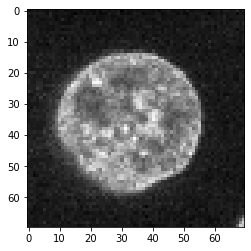

为了演示卷积和反卷积,我们暂时假设这张显示细胞核的图像反映了生物样本中的实际情况。

image = cells3d()[30,1,120:190,80:150]

imshow(image)